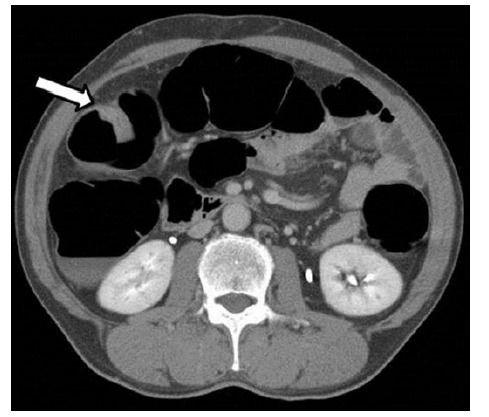

CT 显示肠壁增厚,病变部位诊断为 T2(MP),无证据显示淋巴结转移或远处转移(图 4)

图 4 CT 提示肠壁增厚(箭头处),无淋巴结肿大或远处转移